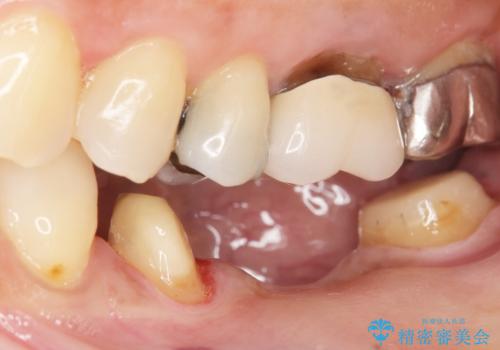

- 奥歯の痛みを主訴に来院された患者様です。

精査したところ、ブリッジの支台歯となっている左下の奥歯(左下7)は大きなう蝕により神経が死んでいました。

根管治療後、メタルボンドブリッジによる補綴治療を行いました。